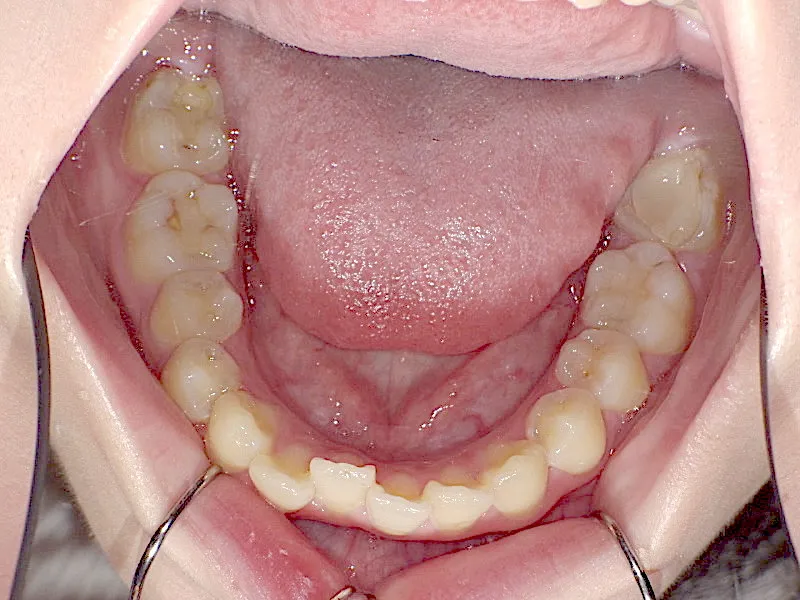

初診時

上下の歯並びがガタガタで口元が出ています。

元々小学生の時にマルチブラケット装置を上下につけ、矯正治療を受けていました。

何年か経過後、ガタガタと口元が気になると受診されました。

後戻りの原因は、リテーナーの装着時間不足、頬杖や、口呼吸などが考えられます。